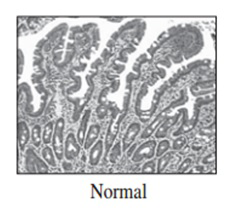

Imágenes tomadas durante la endoscopia digestiva alta y la colonoscopia. Se aprecia una mucosa de aspecto y vascularización normal, sin lesiones visibles. Se progresa con el colonoscopio hasta el íleon. Todo resulta macroscópicamente normal. Se toman biopsias de todos los segmentos explorados.

La endoscopia es el método de elección para el diagnóstico y seguimiento de la EII. Permite una visión macroscópica de la mucosa intestinal y la toma de múltiples biopsias para el estudio histológico.

Realizamos una endoscopia digestiva alta y una colonoscopia a la paciente con toma de biopsias, obteniendo el informe de Anatomía patológica.